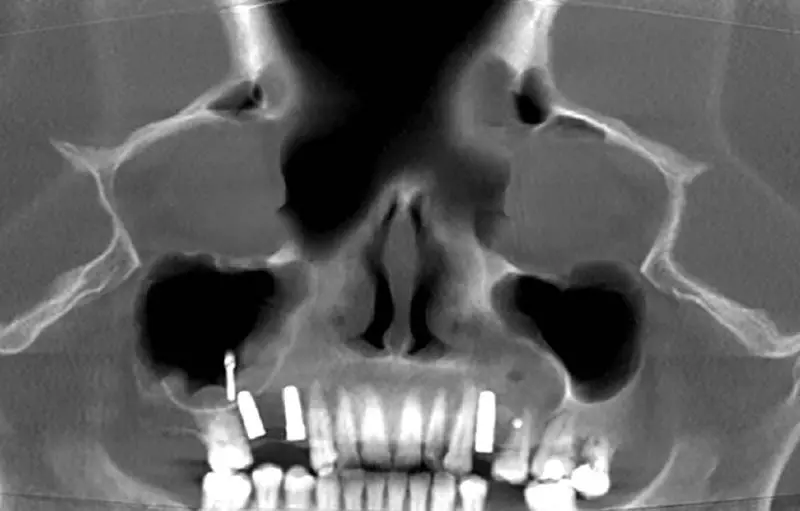

Zdj. 2

Zdj. 3

Przygotowując pacjenta do zabiegu chirurgicznego podniesienia zatoki szczękowej, trzeba przeprowadzić szczegółowy wywiad, badanie podmiotowe oraz dokładne badanie kliniczne-przedmiotowe (linia uśmiechu, przestrzenne stosunki okluzyjne, morfologia tkanek miękkich, ilość tkanek twardych itp.) oraz szczegółowe badania radiologiczne. Diagnostyka radiologiczna dotyczy zarówno ortopantomogramów, zdjęć celowanych, jak i zaawansowanego badania radiologicznego – tomografii komputerowej.

Tomografia komputerowa zatok

Podstawą decyzji o zabiegu chirurgicznym i oceny stanu zatok powinna być tomografia komputerowa, która dostarcza informacji nie tylko o zmianach we wszystkich zatokach, lecz także pozwala ocenić anomalie w budowie sitowia i w kompleksie szczelin ujściowo-przewodowych pomiędzy nosem a jamami zatok. Wskazaniem do wykonania tomografii komputerowej – już w przebiegu ostrego zapalenia zatok jest: brak poprawy po 48–72 godzinach leczenia ostrego zapalenia zatok o ciężkim przebiegu, podejrzenie powikłań zatokopochodnych, zębopochodnych, oczodołowych lub wewnątrzczaszkowych.